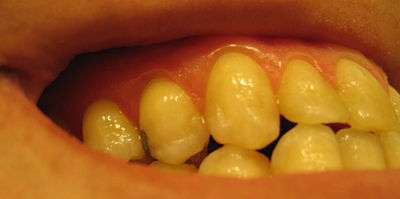

Photograph of the upper right quadrant, showing teeth #4-8, with a DO amalgam on #5. The stippled surface texture of the attached gingiva can be observed. Note how there is no stippling on the marginal gingiva, which is the millimeter or so of gingiva immediately adjacent to the teeth. Click on this photo to see the stippling in greater detail.

The gingiva often possess a textured surface that is referred to as being stippled (engraved points).[1] Stippling only presents on the attached gingiva bound to underlying alveolar bone, not the freely moveable alveolar mucosa. Stippling used to be thought to indicate health, but it has since been shown that smooth gingiva is not an indication of disease, unless it is smooth due to a loss of previously existing stippling.

Stippling is a consequence of the microscopic elevations and depressions of the surface of the gingival tissue due to the connective tissue projections within the tissue.[1] "The degree of keratinization and the prominence of stippling appear to be related."[1] To be more specific, stippling occurs at sites of fusion of the epithelial ridges (also known as rete pegs) and correspond to the fusion of the valleys created by the connective tissue papillae.[2]